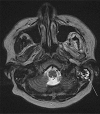

Case report: A 33-year-old man with a history of infracentimetric carcinoma of the lip developed back pain associated with progressive neurological disorders leading to paraplegia. This atypical presentation led to initial misdiagnosis, but radiological and cytological explorations finally confirmed the diagnosis of leptomeningeal and intramedullar secondary spinal cord lesions from his previously treated head and neck SCC. Systemic targeted therapy with epidermal growth factor receptor inhibitor and intrathecal chemotherapy led to prolonged disease stabilization.